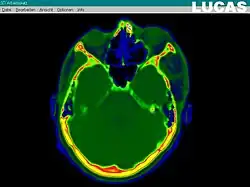

Image analysis and processing

Image analysis involves the manipulation of the patients 3D model to extract relevant information from the data. Using the differing contrast levels of the different tissues within the imagery, as examples, a model can be changed to show just hard structures such as bone, or view the flow of arteries and veins through the brain.